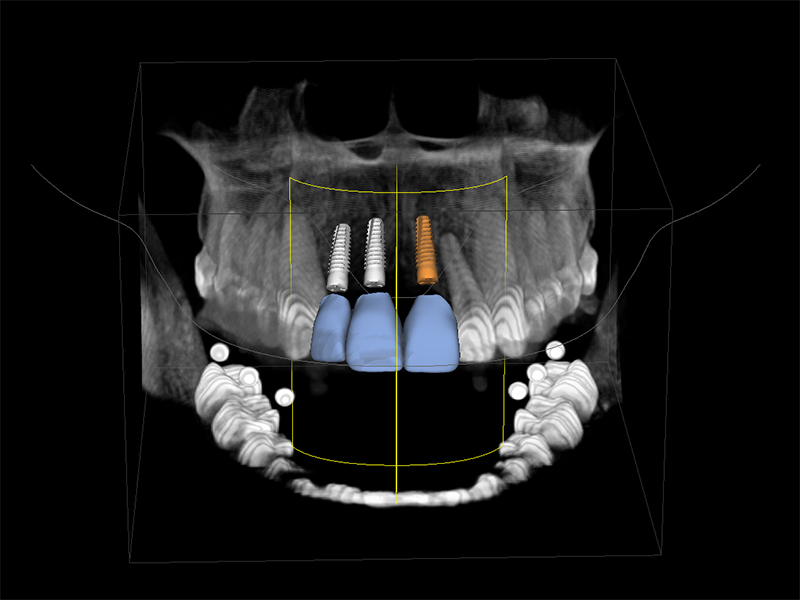

Zahnimplantate werden anhand von moderner virtueller 3D-Planung passgenau geplant und inseriert. Der Vorteil von Implantaten besteht darin, dass festsitzender ästhetischer Zahnersatz auch in solchen Fällen realisiert werden kann, in denen sonst nur herausnehmbare Prothesen möglich wären. Zudem ist im Gegensatz zur Brückenprothetik kein Beschleifen der Nachbarzähne notwendig.